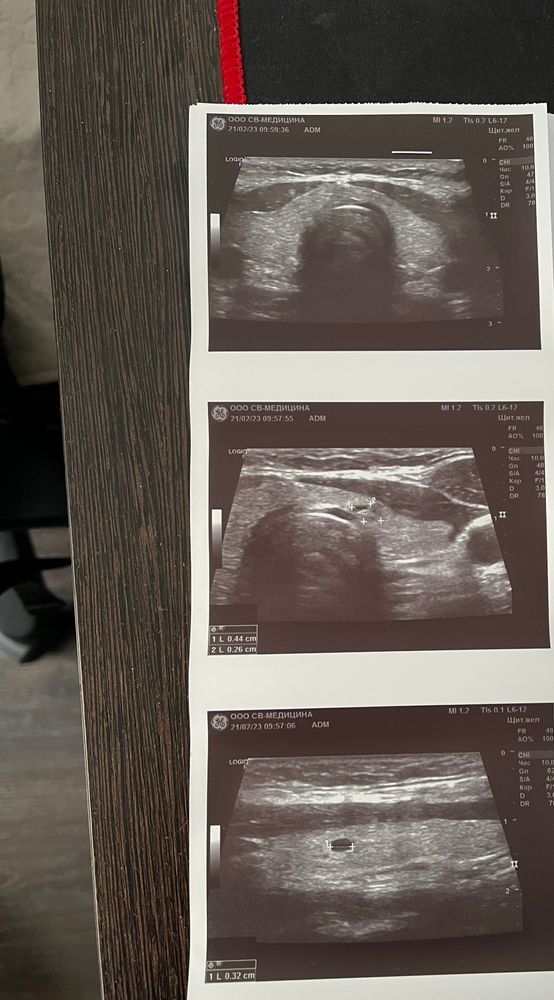

SOS 🛟 Сделала узи щитовидки нашли узел

Феникс, просто планируем и тут на узи сказали , что есть узел я прям испугалась

Света, репродуктолог попросил узи для отчета . Просто анализ отличный пью эутирокс поэтому еще и узи попросила. Так как мы идем сейчас к подготовки к беременности и она сказала, что узи тоже должно быть

Ну узел и узел. Мелкий вобще. Многие с ними живут, они могут проходить и появляться. Большие вот пунктируют